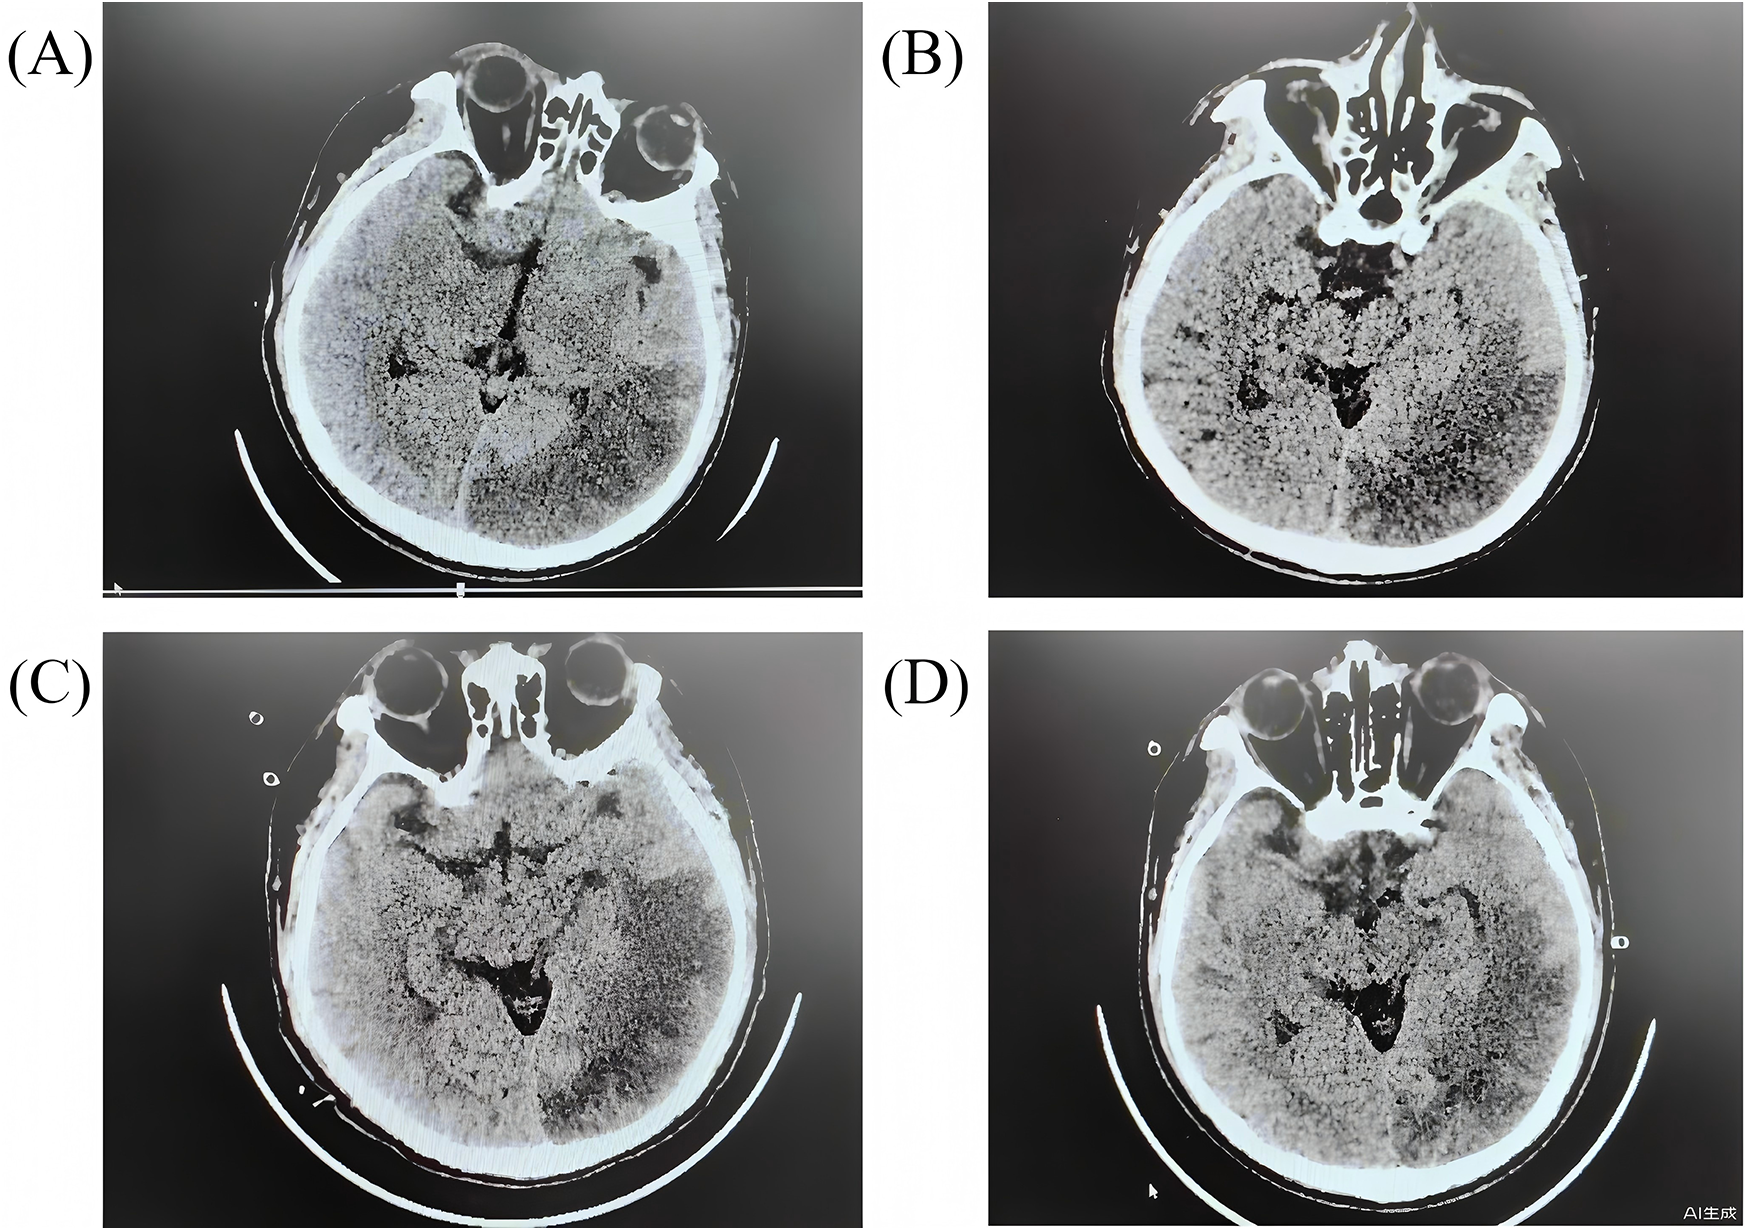

Neurological course

On Day 2, a right pupil 2.5 mm vs. a left pupil 3.5 mm (sluggish on the left) was noted. A stat non-contrast head CT revealed a large acute infarction in the left occipital-temporal (Figure 3A). Neuroprotective medications, including edaravone and butylphthalide, were added. On Day 3, the patient developed signs of central diabetes insipidus. Desmopressin (pitressin) was given, and mannitol was discontinued to avoid exacerbating hypernatremia. Hypothermia was discontinued on Day 4, and the patient was gradually rewarmed to normothermia over the next 24–48 h. By Day 5, sedation was lightened, and attempts at neurologic assessment were made. Remarkably, on Day 7 the patient showed purposeful movements and coherent speech with minimal sedation. Over the next days his orientation improved. Neurological exams eventually normalized with no hemiparesis.

Figure 3

The head CT scans for the patients during hospitalization. (A) day 2 after arrest; (B) day 7 after arrest; (C) day 11 after arrest; (D) day 15 after arrest.

Rehabilitation and follow-up

Complications: brain infarction

The case was complicated by a large ischemic stroke (Figure 3). Neurological injury is the most feared complication of cardiac arrest and ECMO (25). It is not possible to determine whether the stroke occurred during the arrest or during the peri-ECMO period. Fortunately, the infarct was in the left occipitotemporal region, largely non-motor, so that no hemiparesis ensued. The patient's intact neurologic status allowed aggressive therapy to continue. Whether an ECPR patient has an infarct or hemorrhage can be the key determinant of outcome. In this case, early detection and treatment of the infarct (and the absence of hemorrhage) were beneficial. Given his diabetes insipidus and imaging findings, we monitored endocrinologic and metabolic parameters closely. The transient diabetes insipidus was likely central and was promptly treated with desmopressin to prevent hypernatremia and further neural damage. Other organ functions (renal, hepatic) remained stable, which may reflect the protective effect of ECMO perfusion (26).